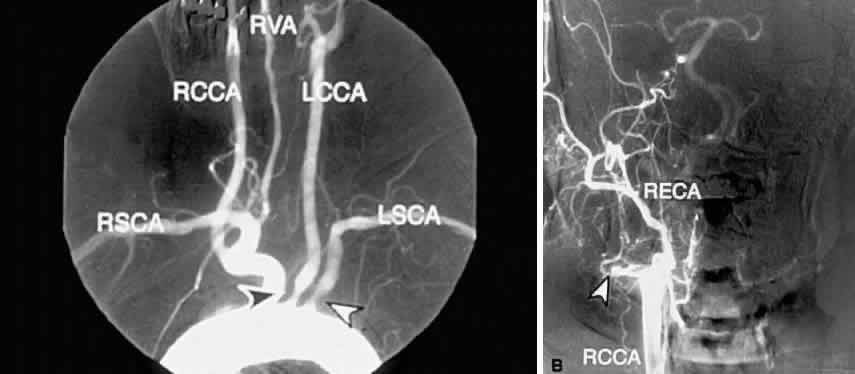

Carotid angiography is performed by selective common carotid arterial injection of a radiopaque contrast dye via transfemoral catheterization. In the traditional technique, the image of the inner luminal silhouette is produced on x-ray emulsion (Fig. 10A and B). More recently, digital images and computerized image enhancement have improved resolution and reduced the amount of contrast dye required.46,47 This method can detect ulcerative lesions, severe stenosis, and formation of mural thrombus. It can also demonstrate collateral circulatory patterns.

Fig. 10. A. Digital subtraction aortogram revealing a 90% atherosclerotic stenosis of the proximal left common carotid artery (black arrowhead) and 80% stenosis of the proximal left subclavian artery (white arrowhead). RSCA, right subclavian artery; RCCA, right common carotid artery; RVA, right vertebral artery; LCCA, left common carotid artery; LSCA, left subclavian artery. B. Digital subtraction angiogram with a right common carotid injection from the same patient. There is complete occlusion of the right internal carotid artery due to atherosclerosis (white arrowhead). The right external carotid artery (RECA) and the right common carotid artery (RCCA) fill normally.

The most serious complications of carotid angiography are aortic or carotid artery dissection, embolic stroke, and myocardial infarction.48 Other complications include dye reactions, renal injury, hematoma, pseudoaneurysm, and arterial thrombosis. Carotid angiography carries a 1% risk of morbidity and 0.06% risk of mortality. As with all tests, the advantages of selective carotid angiography must be weighed against the possible risks.

Despite its expense and low but definite morbidity rate, carotid angiography remains the most reliable method of assessing atherosclerotic carotid disease,38 and it serves as the “gold standard” in the evaluation of all other tests of the carotid arteries.

Ophthalmic symptoms, due to ocular hypoperfusion from occlusion of the carotid artery, are seen in 15% of cases.59 These ophthalmic changes may be identical to those of ocular ischemic syndrome caused by carotid atherosclerotic disease (see Figs. 5 and 6).60,61 Arteriography of the aortic arch region, showing smooth-walled areas of stenosis and dilation, is usually necessary to confirm the diagnosis (Fig. 11). Collateral circulation, due to the chronicity of the stenosis, is usually prominent.

Fig. 11. Digital subtraction thoracic angiogram of the aortic arch and its major branches in the same patient with Takayasu's arteritis as shown in Figures 5 and 6. The right common carotid artery shows nearly complete occlusion (white arrowhead). The left common carotid artery shows complete occlusion with extensive collateral flow (black arrowhead). (Courtesy Travis A. Meredith, MD, St. Louis MO)